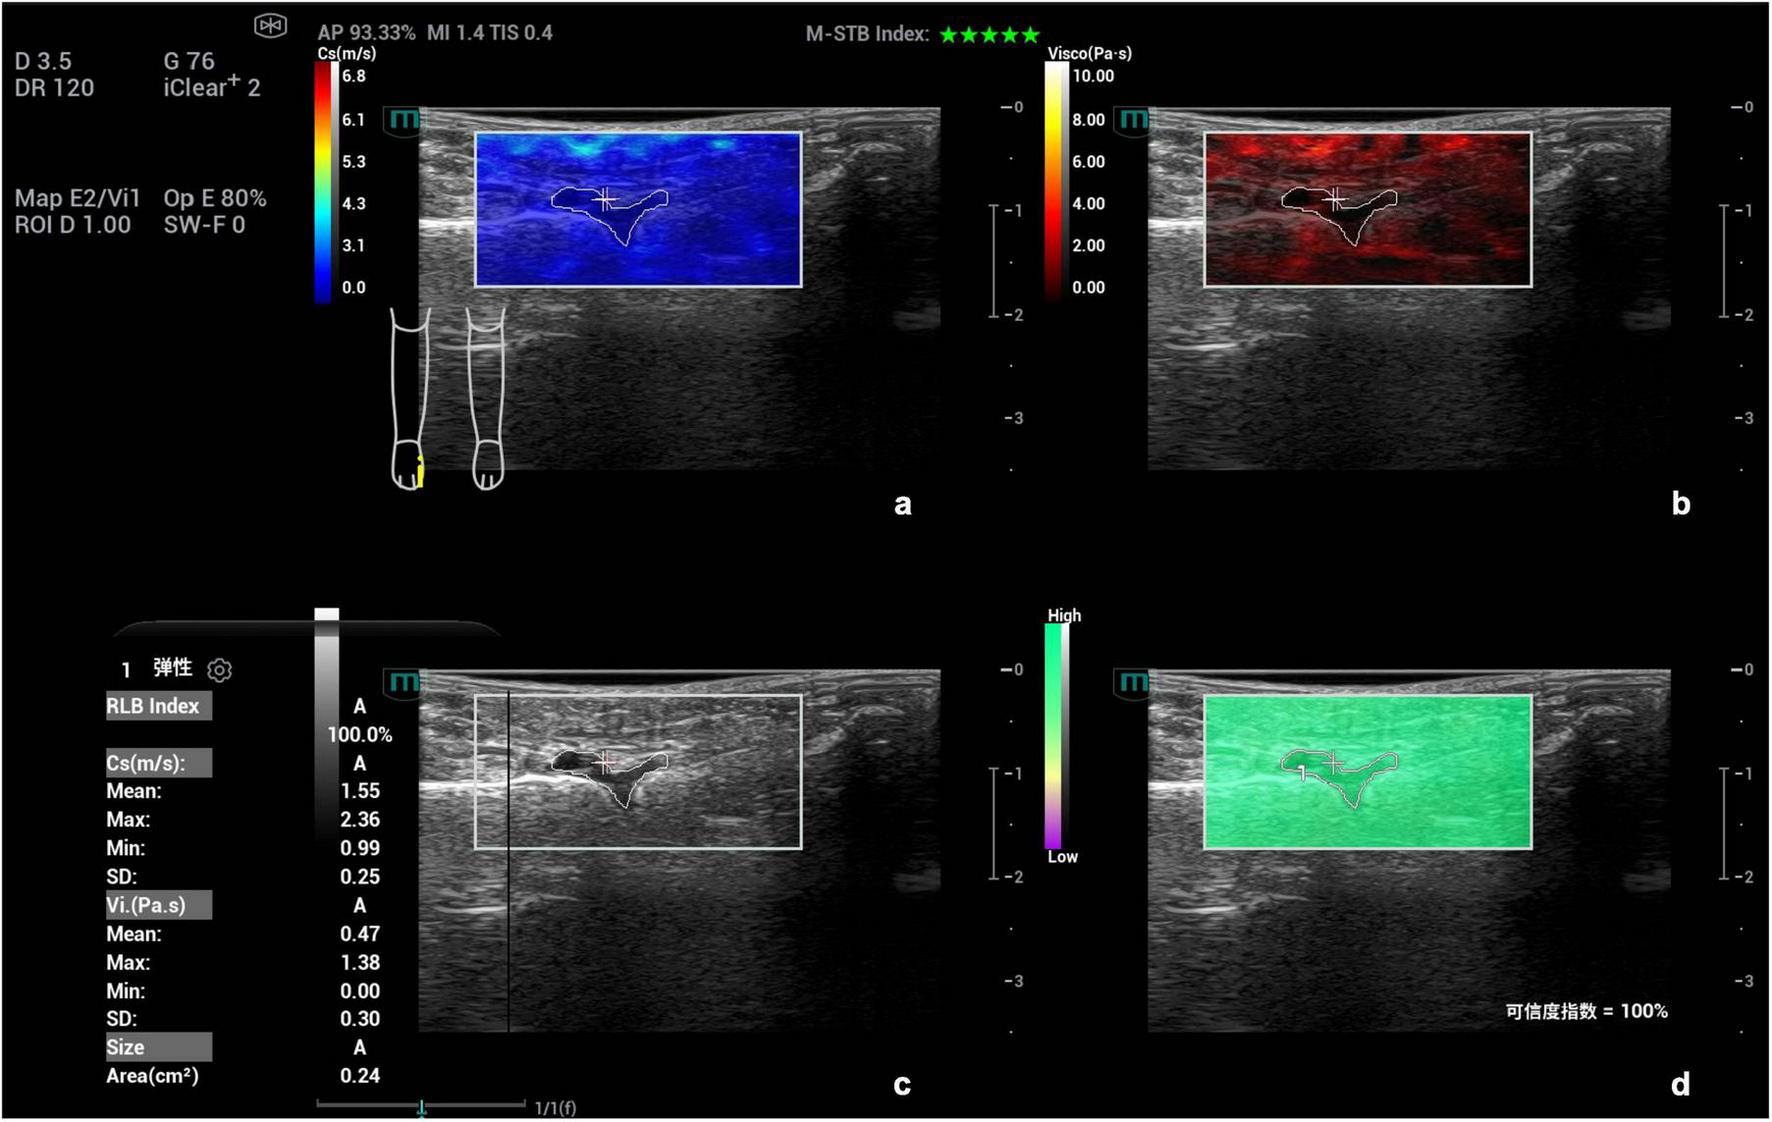

FIGURE 2

Schematic diagram of viscoelastic images (measurement of shear wave velocity and viscosity coefficient in the first metatarsophalangeal joint of the right foot). (a) (top left) Shear wave elasticity image; (b) (top right) Viscosity coefficient image; (c) (bottom left) Grayscale ultrasound image; (d) (bottom right) Reliability map (RLB).

Images were analyzed under the four-panel mode of viscoelastic imaging (Figures 2, 3). On the gray-scale ultrasound image, region of interest (ROI) was delineated along the edge of the thickened synovial, and the corresponding ROI was synchronously displayed on the shear wave elasticity and viscosity images. The system automatically acquired quantitative parameters: shear wave elastic parameters (reflecting tissue stiffness) including the mean, maximum, minimum, and standard deviation of shear wave velocity (C, m/s); viscosity imaging parameters (reflecting tissue viscosity) including the mean, maximum, minimum, and standard deviation of viscosity coefficient (V, Pa⋅s) and dispersion coefficient [D, (m/s)/kHz]. A total of 12 parameters were obtained. Image acquisition and data measurement were repeated 5 times, and the mean values were recorded and calculated.

Among the single parameters, Cmean showed the highest diagnostic efficacy, with an AUC of 0.836 (95% CI 0.774∼0.897). The optimal cut-off value was 2.36 m/s (Figures 4, 5), at which the sensitivity and specificity for diagnosing AG were 81.4% and 71.6%, respectively. The AUC of the GEE model was 0.885 (95% CI 0.833∼0.938), with an optimal cutoff value of 0.41, and the corresponding sensitivity and, specificity for diagnosing AG were 87.1% and 76.5%, respectively (Table 4).

Ultrasound viscoelastic image of the left elbow joint in a patient with acute gout (AG). A 69-year-old male patient. Ultrasound viscoelastic imaging showed that the thickened synovium of the left elbow joint had a Cmean of 2.98 m/s (>cut-off value of 2.36 m/s) and a Dmean of 8.47 (m/s)/kHz [>cutoff value of 4.35 (m/s)/kHz].